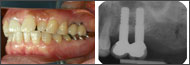

| 1ピースでの審美性の工夫(2) | ||

![]() 1999/10/04 左下6 5SM植立、2000/01/26 左下7 #568植立、2000/8/18 MBCr装着 |

![]() 2001/01/26 右上2 4LM植立、2001/10/31 右上2,右上1,左上1,左上2 MBCr着 |

![]() 2006/08/23 右上2 植立5Y1M後、左下6 植立7Y11M後、左下7 植立6Y7M後、前歯、臼歯共に審美性を保っている。右上2は、右上1,左上1,2などの天然歯と何ら遜色はない。 |